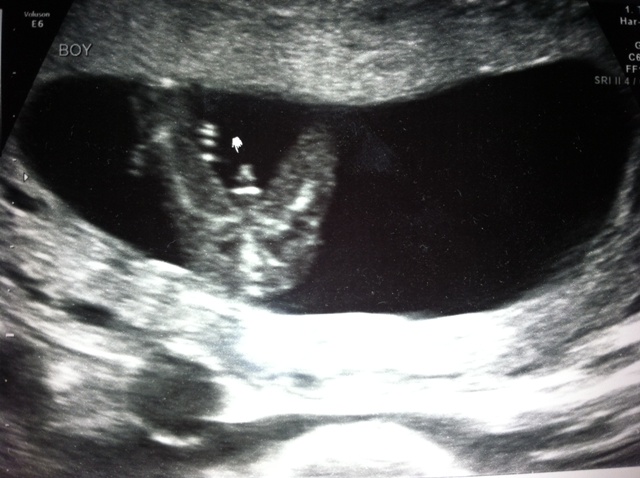

Take a look at these pics and tell me what you think. The profile shot is from 12w1d but I don't think you can see the nub (however I'm bad at this, so who knows). The potty shot is from 13w1d which I know is super early for a potty shot. However, the tech seemed to be very certain that it is a boy. What do you think? I'm just looking for guesses/opinions, I will find out next week either way but I want to see what you think. ;-) Thanks so much!!

Attachment 7961

Looks like a boy. Congrats.

Defo looks boy to me by that potty shot!